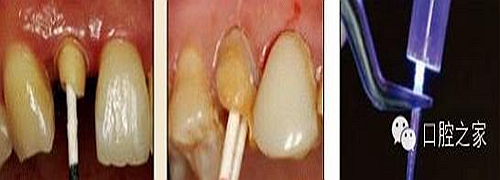

6.纖維樁的試放和裁截

纖維樁試放時應(yīng)選用鑷子夾持將其插入預(yù)備根管,就位時無阻力且稍有匡量(圖 13),禁用污染手套或止血鉗夾持(圖 14)。試放合適后應(yīng)按所需長度用細(xì)顆粒金剛砂車針切割裁截。切勿使用技工鉗或粗顆粒金剛砂片(圖 15),以免造成纖維撕裂散開,使纖維樁機械性能降低。由于在裁剪過程中有可能造成樁的表面污染,也可以粘接固位后再進(jìn)行裁剪。臨床操作時,應(yīng)在樹脂核成型后,頰、舌、合面分別光照20s,在完成預(yù)備體時將其磨除(圖16)。 ##pages##